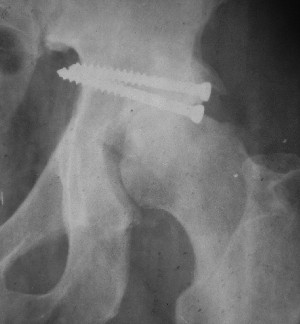

Привет! Вот недавно прооперировали похожий на ваш случай - впадина + шейка (правда у нас впадина поперечный+задний край). После травмы прошло 4 недели. мужчине 46 лет. С такой комбинацией все показания к первичному протезированию. Морально и технически мы к этому уже созрели.Но больной не собрал денег на протез. Выполнили остеосинтез впадины и шейки, прекрасно понимая, что головка вскоре рассосется, мы хотя бы надемся что к этому времени таз срастется, как говорится создали все условия для дальнейшего протезирования (может, и протез в последующем подешевле будет, в смысле, без укрепляющего кольца?). Привет Рункову!

Привет Алекей! Сделано неплохо, поздравляю, хотя второй винтик можно было бы и подлиннее в шейку загнать! Пара вопроов: доступ такой же? головка была свободной или висела на капсуле?

Согласен, можно было и подлиннее. Доступ такой же - чрезвертельный, только разрез кожи прямой (а не Y, чего то я разницы не ощущаю). Головка была абсолютно свободной (то есть во время остеосинтеза таза лежала в стакане и не мешалась). Шансов, что она прирастет 0,00001%. Хотели даже выбросить, но привинтили как временный биологический протез (читай свободный трансплантат), чтоб на период срастания таза бедро проксимально не ушло (может ортопеды потом спасибо скажут). Ну а у вас первичное протезирование при переломе впадины тоже пока полько в планах?